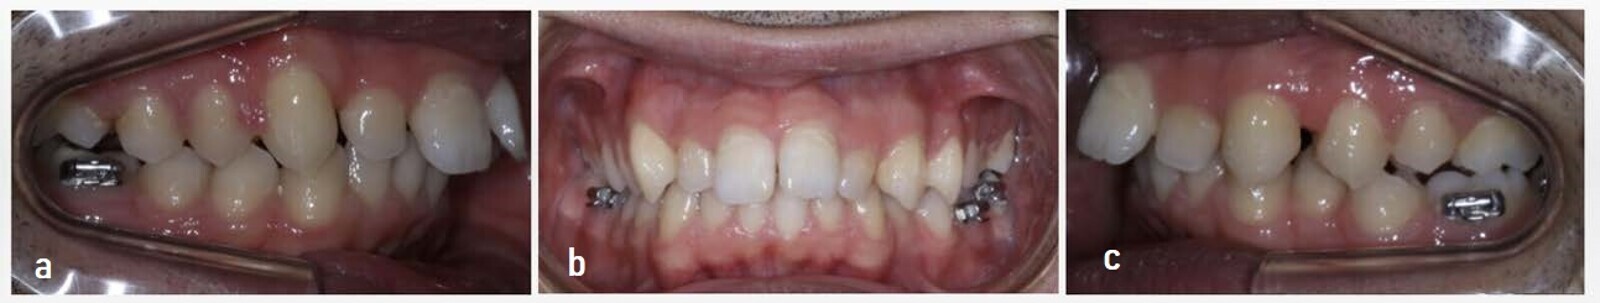

One year after placement of the fixed appliances, the treatment concluded (Figs. 16 & 17). Removable transparent retainers were manufactured to maintain the results. Considering the treatment stage with the CMA and the subsequent stage with the fixed multi-bracket appliances, the total time needed for the correction was one year and seven months.

The outcome achieved was satisfactory to the patient (Table 1; Figs. 18–21). A well-aligned occlusion had been created with a significant reduction of the overjet and with a Class I molar and canine relationship. The traction and de-rotation achieved by the Class II CMA had helped to reduce the overjet. The position of both maxillary and mandibular central incisors exhibited significant changes due to the maxillary incisor retroclination and the mandibular incisor proclination. This explained the increase of the ANB angle at the end of the treatment. As for the inter-incisal angle, the treatment managed to set its value within standard parameters (122°). The correction of the mandibular incisor resulted in a decrease in the labial protrusion, and this was reflected via an improvement in the profile. The changes produced at the skeletal level were not significant, since growth had already been completed at the time of treatment.

The final intra-oral and extra-oral photographs showed a bilateral change in the posterior and anterior dimensions (Fig. 25). Parabolic and symmetrical arches and a great improvement in the overjet, which was now normal (1 mm), were evident. The patient went from a convex profile to a profile with the upper and lower lips in a better position.